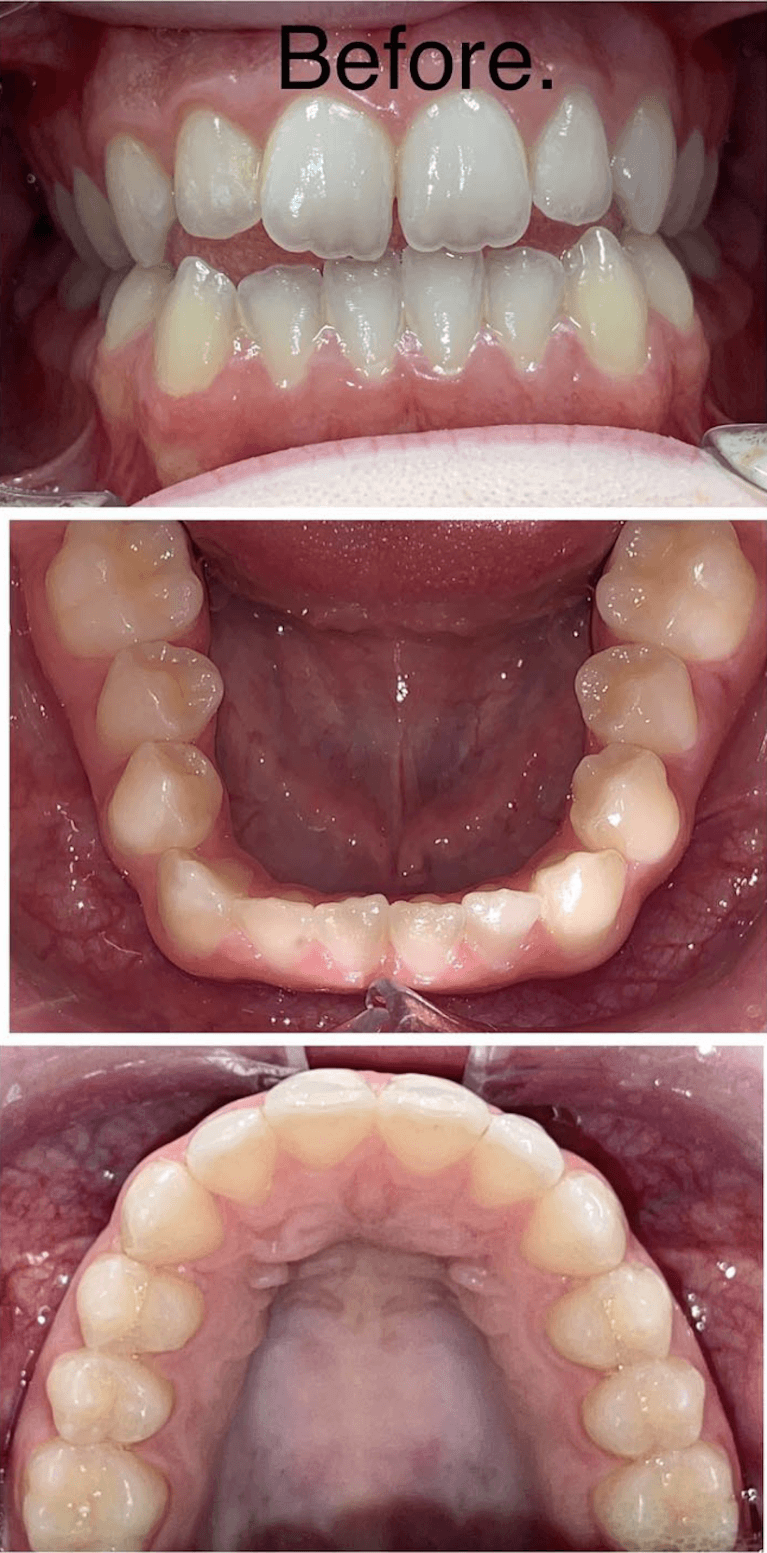

Before and after with Invisalign orthodontic treatment. Pictures taken with different phones at different setting. Used total of 27 aligners/trays. Treatment time 13.5 months